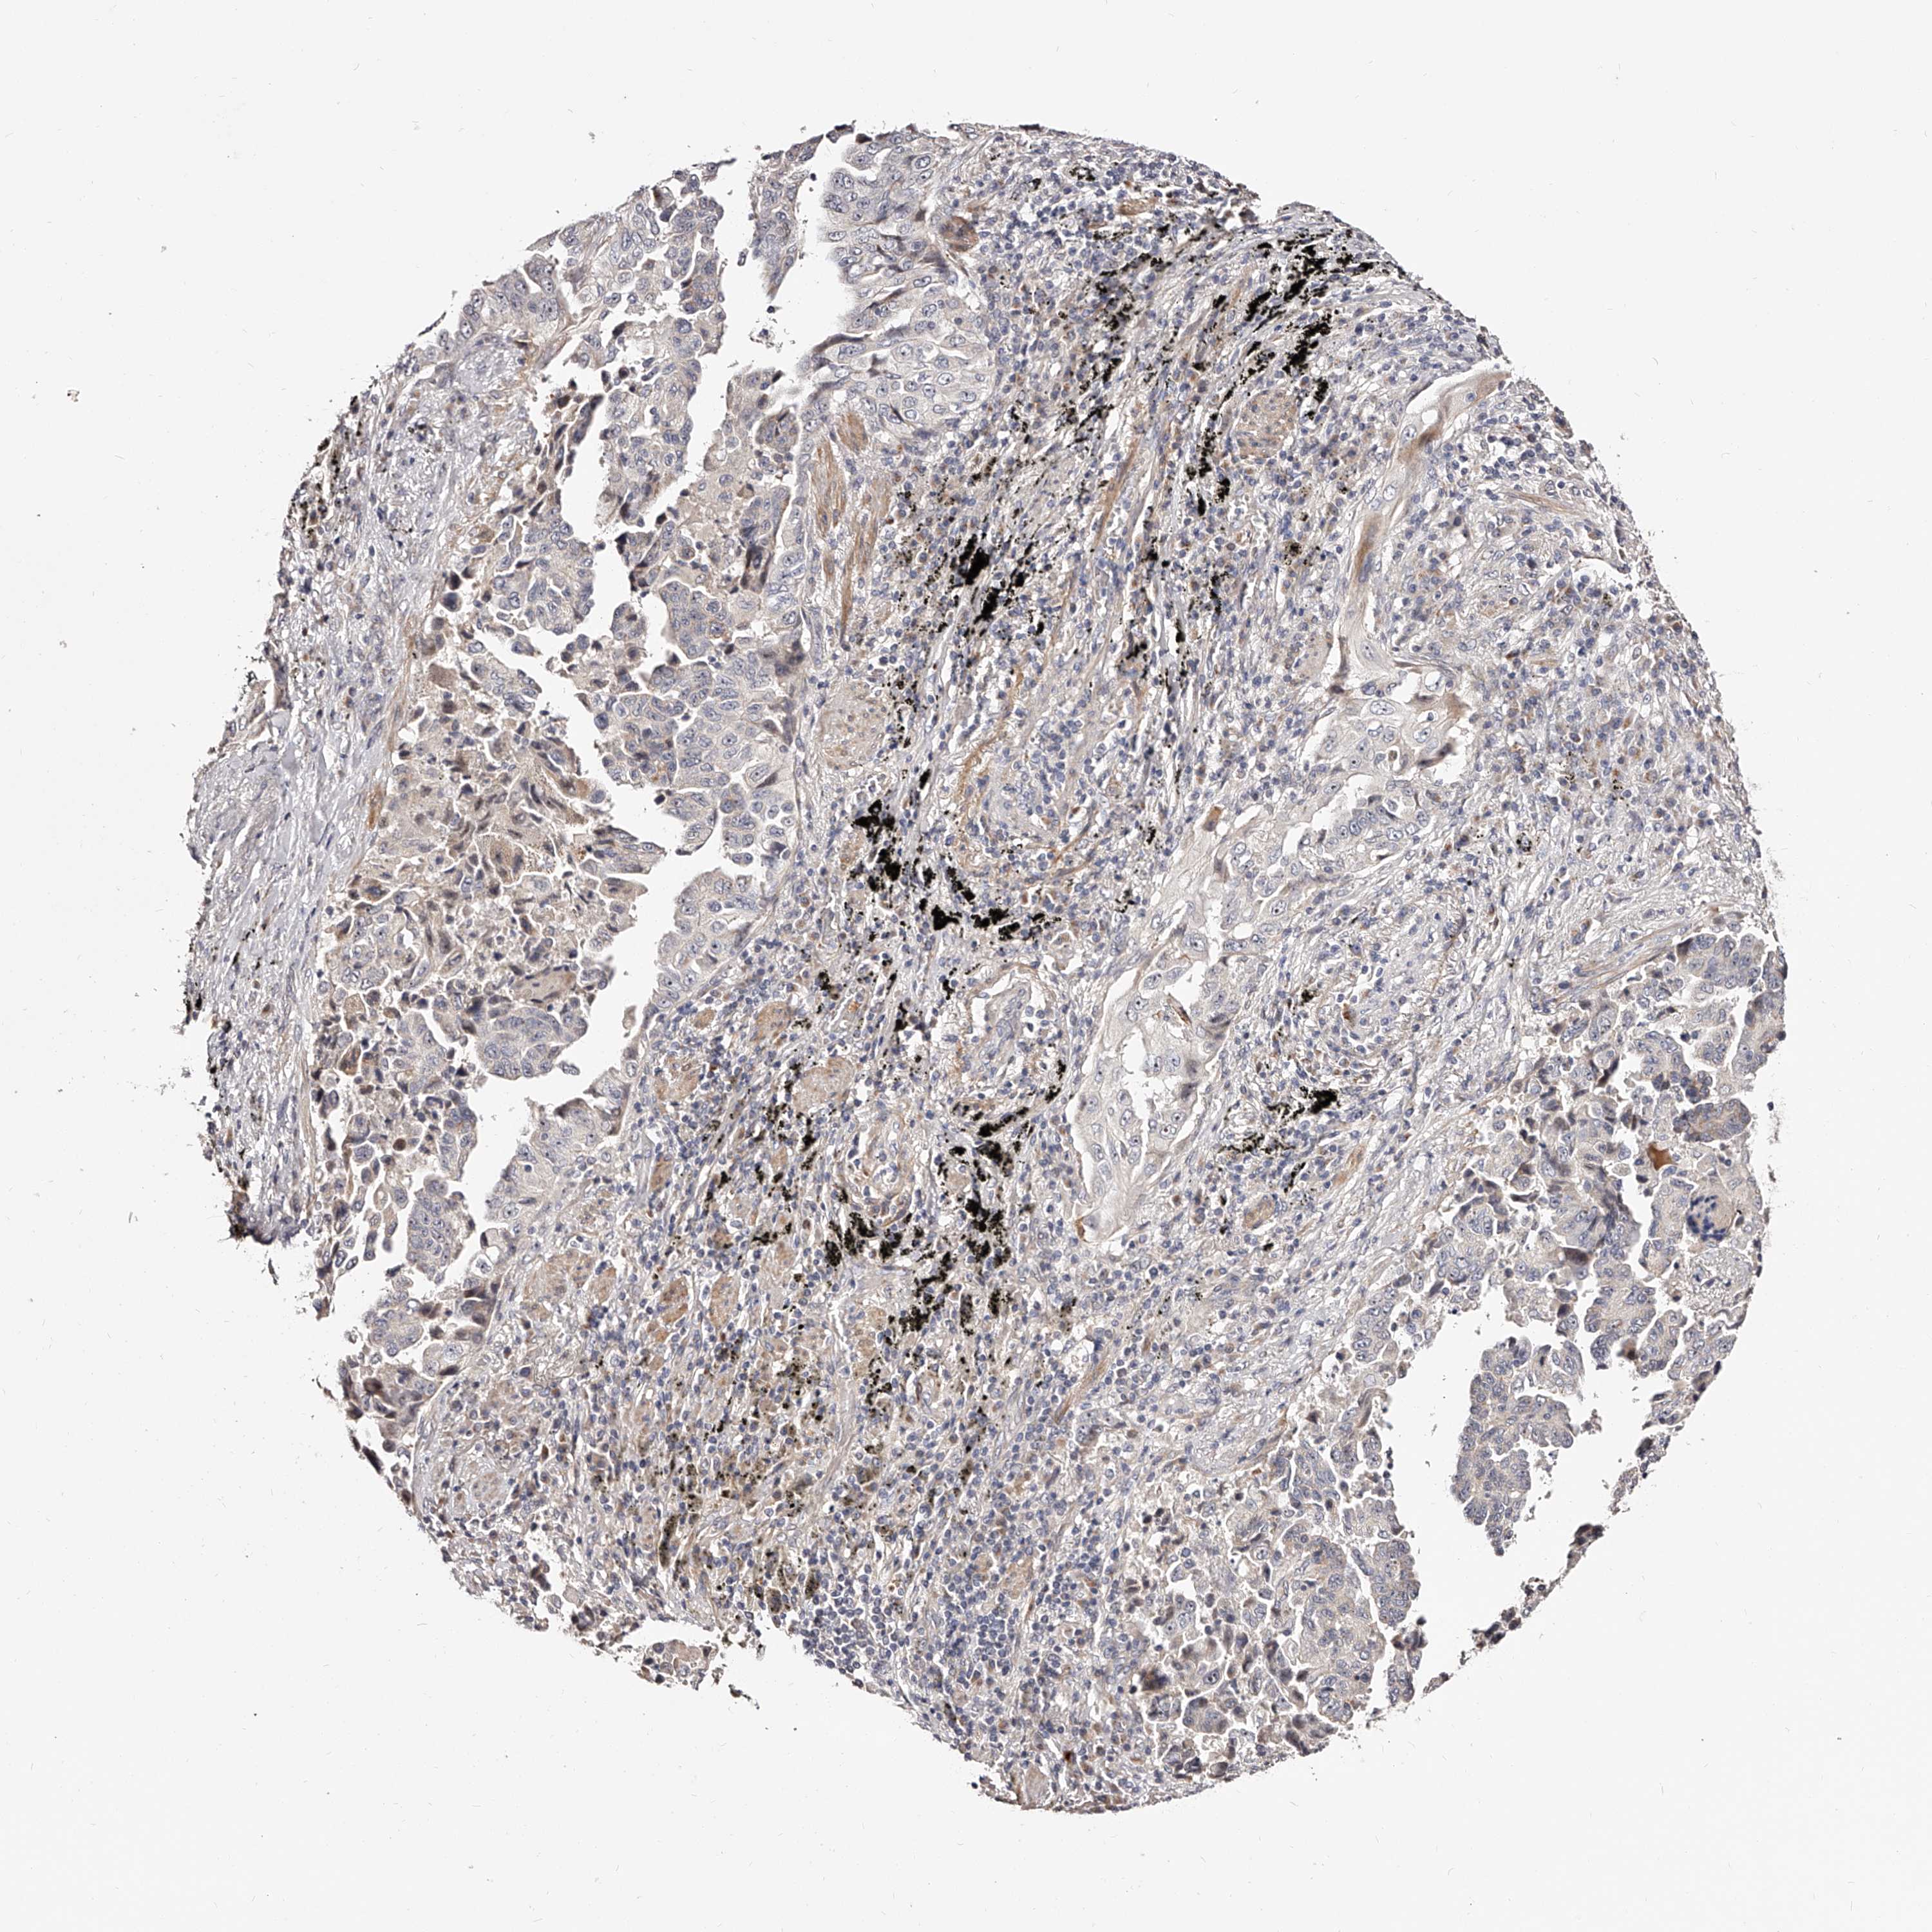

LUNG SQUAMOUS CELL CARCINOMA (TCGA) - Interactive survival scatter ploti

The Survival Scatter plot shows the clinical status (i.e. dead or alive) for all individuals in the patient cohort, based on the same data that underlies the corresponding Kaplan-Meier plots. Patients that are alive at last time for follow-up are shown in blue and patients who have died during the study are shown in red.

The x-axis shows the expression levels (FPKM) of the investigated gene in the tumor tissue at the time of diagnosis. The y-axis shows the follow-up time after diagnosis (years). Both axes are complimented with kernel density curves demonstrating the data density over the axes. The top density plot shows the expression levels (FPKM) distribution among dead (red) and alive patients (blue). The right density plot shows the data density of the survived years of dead patients with high and low expression levels respectively, stratified using the cutoff indicated by the vertical dashed line through the Survival Scatter plot. This cutoff is automatically defined based on the FPKM cutoff that minimizes the p-score. The cutoff can be changed by dragging the vertical line or by entering a cutoff value in the square labeled "Current cut-off".

Under the Survival Scatter plot the p-score landscape (black curve; left axis) is shown together with dead median separation (red curve; right axis). Dead median separation is the difference in median mRNA expression between patients who have died with high and low expression, respectively. It is calculated as follows: median FPKM expression of dead patients with high expression - median FPKM expression of dead patients with low expression. This is intended to aid the user in visually exploring custom cutoffs and the associated p-scores and dead median separation.

Individual patient data is displayed and can be filtered by clicking on one or more of the category buttons on the top of the page. Categories describing expression level and patient information include: high, low, alive, dead, female, male and tumor stages. The scale of the x-axis can be toggled between linear and log-scale by clicking on the "x log" button. Mouse-over function shows TCGA ID, patient information and mRNA expression (FPKM) for each patient.

& Survival analysisi

Kaplan-Meier plots summarize results from analysis of correlation between mRNA expression level and patient survival. Patients were divided based on level of expression into one of the two groups "low" (under cut off) or "high" (over cut off). X-axis shows time for survival (years) and y-axis shows the probability of survival, where 1.0 corresponds to 100 percent.

ZNF502 is not prognostic in Lung Squamous Cell Carcinoma (TCGA)

: 1.48